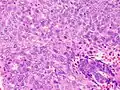

Clear cell carcinoma

Clear cell carcinoma is a Type II endometrial tumor that makes up less than 5% of diagnosed endometrial cancer. Like serous cell carcinoma, it is usually aggressive and carries a poor prognosis. Histologically, it is characterized by the features common to all clear cells: the eponymous clear cytoplasm when H&E stained and visible, distinct cell membranes.[46] The p53 cell signaling system is not active in endometrial clear cell carcinoma.[15] This form of endometrial cancer is more common in postmenopausal women.[20]